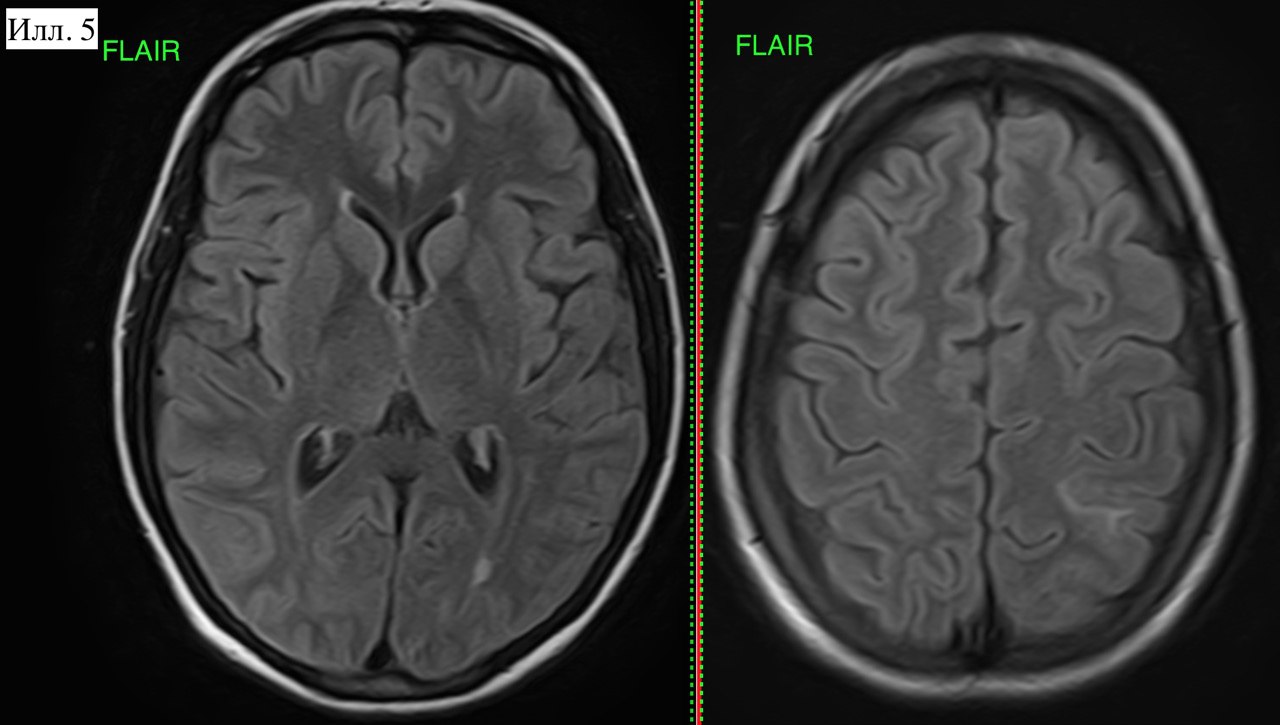

Случай 123-продолжение. #КТ #МРТ #мозг #ОбучающиеМатериалы #СложныйСлучай

Состояние обратимое при своевременной коррекции АД, что и продемонстрировала контрольная МРТ через 5 суток (илл. 5 и 6). При массивном поражении и/или не эффективном лечении возможен переход отдельных очагов в ишемические инсульты (стрелки на илл. 6). В данном случае, речь не идет об отрицательной динамике. ЗОЭ была и разрешилась, единичные мелкие инфаркты - это самостоятельное явление, спровоцированное ЗОЭ, но не являющееся его частью.

Илл. 5. Та же пациентка через 5 суток. Остались отедльные участки отека - сформировавшиеся очаги ОНМК